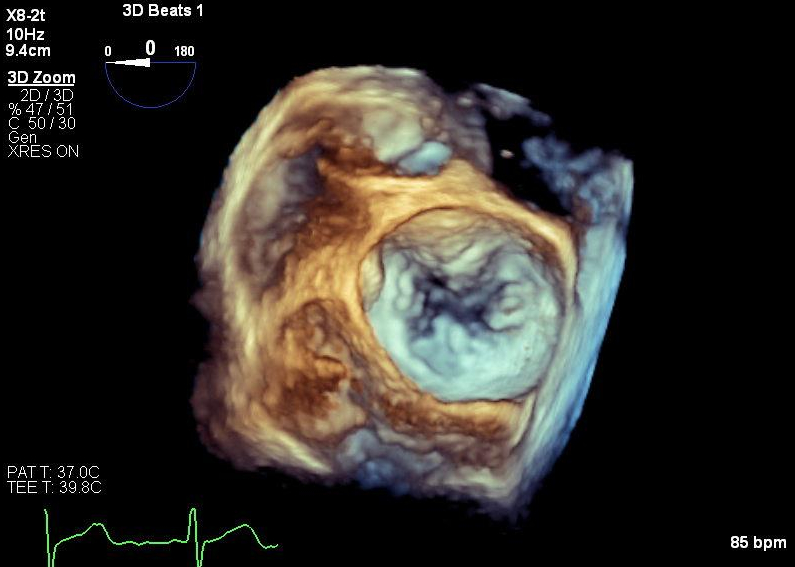

Transthoracic echocardiography (TTE) revealed severe basal septal hypertrophy (1.7cm) and systolic anterior motion (SAM) of the anterior mitral valve leaflet (peak LVOT gradient 104 mm Hg; Figure 1). The patient was treated with metoprolol but presented again one month later with recurrent postural syncope. The metoprolol dosage was increased, and the patient was initiated on mavacamten.